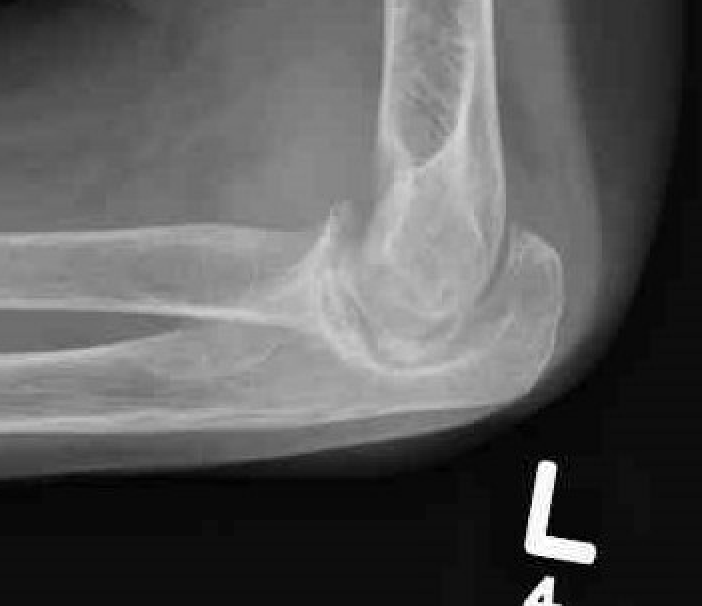

Xray

Articular destruction/ cysts / osteopenia /structural bone loss